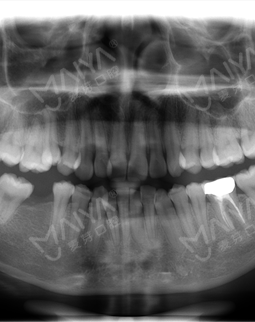

经朋友介绍来矫正,医生说了一堆安慰我年龄不是问题,服务态度好好哦~另外说牙齿非常不整齐,右下有个磨牙缺失不能种,为了我的工作考虑,采取了隐形正畸技术,拔了智齿,然后排齐牙齿,上图,这就是露牙后的效果,总感觉哪里怪怪的~~